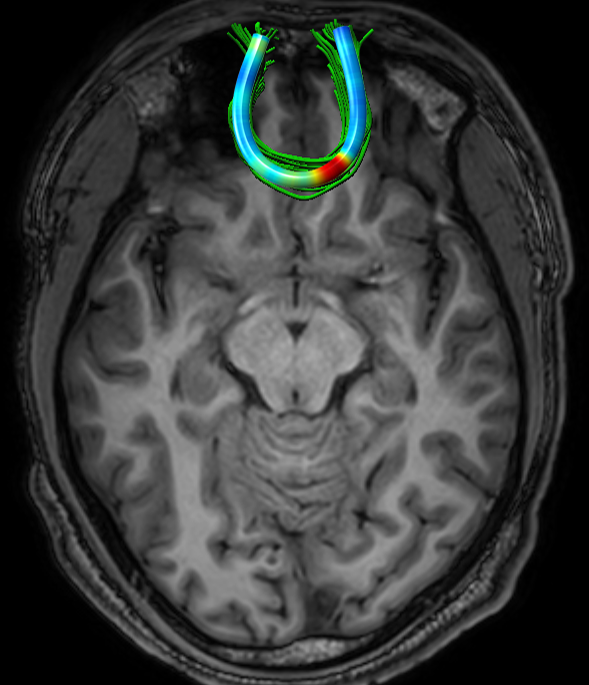

We performed pairwise comparison between two scans of a 32-year-old basketball player, diagnosed with mild occipital traumatic brain injury and frontal hemorrhage due to contrecoup impact, acquired one week and 6 months post-injury. The hemorrhagic lesion at the frontal right hemisphere of the player is no longer visible in the FLAIR image acquired 6 months after injury (Fig. 2a). Local differences between corresponding, longitudinal FA- and MD-FFDD profiles of the FMT (chosen due to its proximity to the lesion area) are shown in Fig. 2d. Figs. 2b-c present color-coded FMT to visually demonstrate these differences. Results show significant longitudinal variability at the right hemisphere part of the tract, corresponding to the lesion area, and relatively minor differences along the rest of the tract. These results should be considered as a proof of concept, validating the FFDD analysis results for the detection and localization of mTBI-related variabilities between fiber bundles.

| ONE WEEK | ![]() |

![]() |

FA-FFDD |

| 6 MONTHS | ![]() |

MD-FFDD |

| (a) FLAIR | (b) FA-FFDD | (c) MD-FFDD | (d) Local Differences |